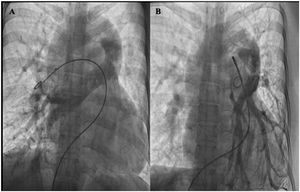

En nuestro caso presentamos a una paciente de 30 años, sin intervenciones previas, con antecedentes de acropaquias desde los 6 años, sin otro síntoma. Fue derivada a nuestra institución con historia de disnea de medianos esfuerzos, palpitaciones, dolor torácico y deterioro de la clase funcional de 2 meses de evolución. En la radiografía de tórax se observó flujo pulmonar aumentado y cardiomegalia a expensas de las cavidades derechas, imagen en «muñeco de nieve» (fig. 1). En el ecocardiograma se evidenció conexión anómala total de venas pulmonares variedad supracardíaca a través de una vena vertical sin obstrucción, comunicación interauricular tipo ostium secundum, dilatación de cavidades derechas y presión sistémica estimada de la arteria pulmonar de 69mmHg. Se complementaron los estudios con tomografía computarizada por sospecha de tromboembolismo pulmonar, donde se encontró drenaje anómalo de todas las venas pulmonares derechas, las del lóbulo inferior y lingulares izquierdas, las cuales confluyen en un colector común horizontal, las venas pulmonares del lóbulo superior izquierdo confluyen en la unión del colector horizontal y longitudinal. Posteriormente, por medio del colector longitudinal izquierdo drenan a la vena innominada, y esta en la cava superior, desembocando en la aurícula derecha (fig. 2). Se descartó tromboembolismo pulmonar y trombosis venosa profunda en las extremidades inferiores. Se sometió a cateterismo cardiaco por vía femoral derecha, donde se determinó salto oximétrico en la vena cava superior y desaturación sistémica con relación a la vena pulmonar (aorta-PaO2: 53mmHg, SaO2 90% vs. vena pulmonar-PaO2: 87mmHg, SaO2 98%). En levofase el retorno venoso pulmonar derecho e izquierdo va hacia un colector, que desemboca en la vena vertical-innominada y posteriormente desemboca en la vena cava superior, con opacificación del atrio derecho y paso de medio de contraste al atrio izquierdo (AI) a través de un defecto septal auricular (fig. 3).